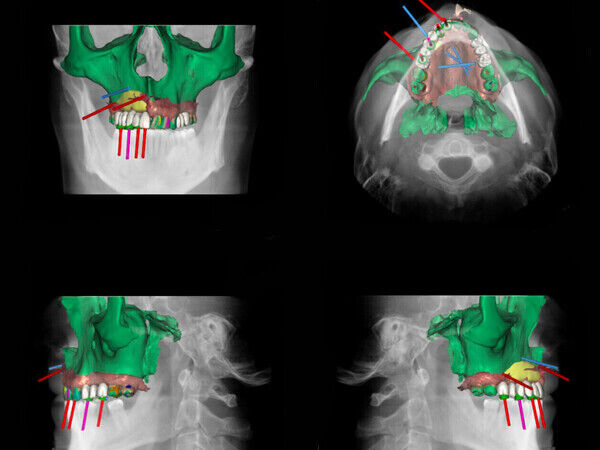

- In Zusammenarbeit mit Zahnärzten wurde für einen Patienten, der schwere Kieferverletzungen erlitt, ein Implantat entwickelt, das sich gleichzeitig für Zahnersatz eignet. Dieses Implantat wird die volle Funktion seines Kiefers wiederherstellen.